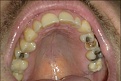

heute haben die ersten meiner acht Amalgamfüllungen ausgedient - und ich habe zwei weitere offene Zähne (24, 26). Hier mal zwei Bilder, links aus dem Jahr 2013 (habe ich hier schon mal eingestellt), und rechts von eben:

Klicke auf die Grafik für eine vergrößerte Ansicht

Name: Ralph_Zähne-Oberkiefer3.jpg

Ansichten: 2

Größe: 40,0 KB

ID: 27941 Klicke auf die Grafik für eine vergrößerte Ansicht

Name: 2015-01-23_Ralph_Zähne-Oberkiefer.jpg

Ansichten: 1

Größe: 169,0 KB

ID: 27942

Die Zähne sehen unter den Füllungen gut aus - Karies hat sich keine gebildet. Auch waren die Füllungen mit Zement unterfüttert, so dass das Amalgam nicht direkt mit dem Dentin in Berührung stand. Da ich sowohl während der Entfernung als auch unmittelbar danach keine Schmerzen habe, bleiben die Zähne offen.